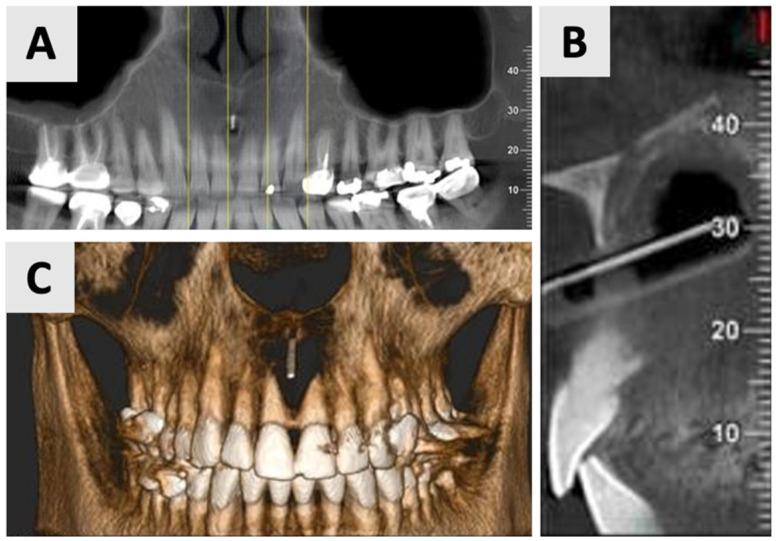

A 35-year-old male patient presented with a large periapical cystic lesion in the maxillary anterior region. Treatment involved marsupialization followed by cyst enucleation and GBR using a resorbable magnesium membrane and bovine xenograft. The magnesium membrane served as a structural support to bridge the bony discontinuity in the palatal bone. Cone-beam computed tomography (CBCT) was used for diagnosis, treatment planning, and follow-up assessments. At 16 months post-treatment, CBCT imaging revealed significant bone regeneration, with restoration of the palatal contour and cortication of the palatal wall. Clinical examination showed asymptomatic teeth with normal mobility and optimal soft tissue healing.

一名35岁男性患者上颌前部出现一个大的根尖囊性病变。治疗包括袋形术,随后进行囊肿摘除术,并使用可吸收镁膜和牛异种移植物进行引导骨再生。镁膜作为一种结构支撑物,用于桥接腭骨的骨不连续处。锥形束计算机断层扫描(CBCT)用于诊断、治疗计划制定和随访评估。治疗后16个月,CBCT成像显示骨再生显著,腭轮廓恢复,腭壁皮质化。临床检查显示牙齿无症状,松动度正常,软组织愈合良好。